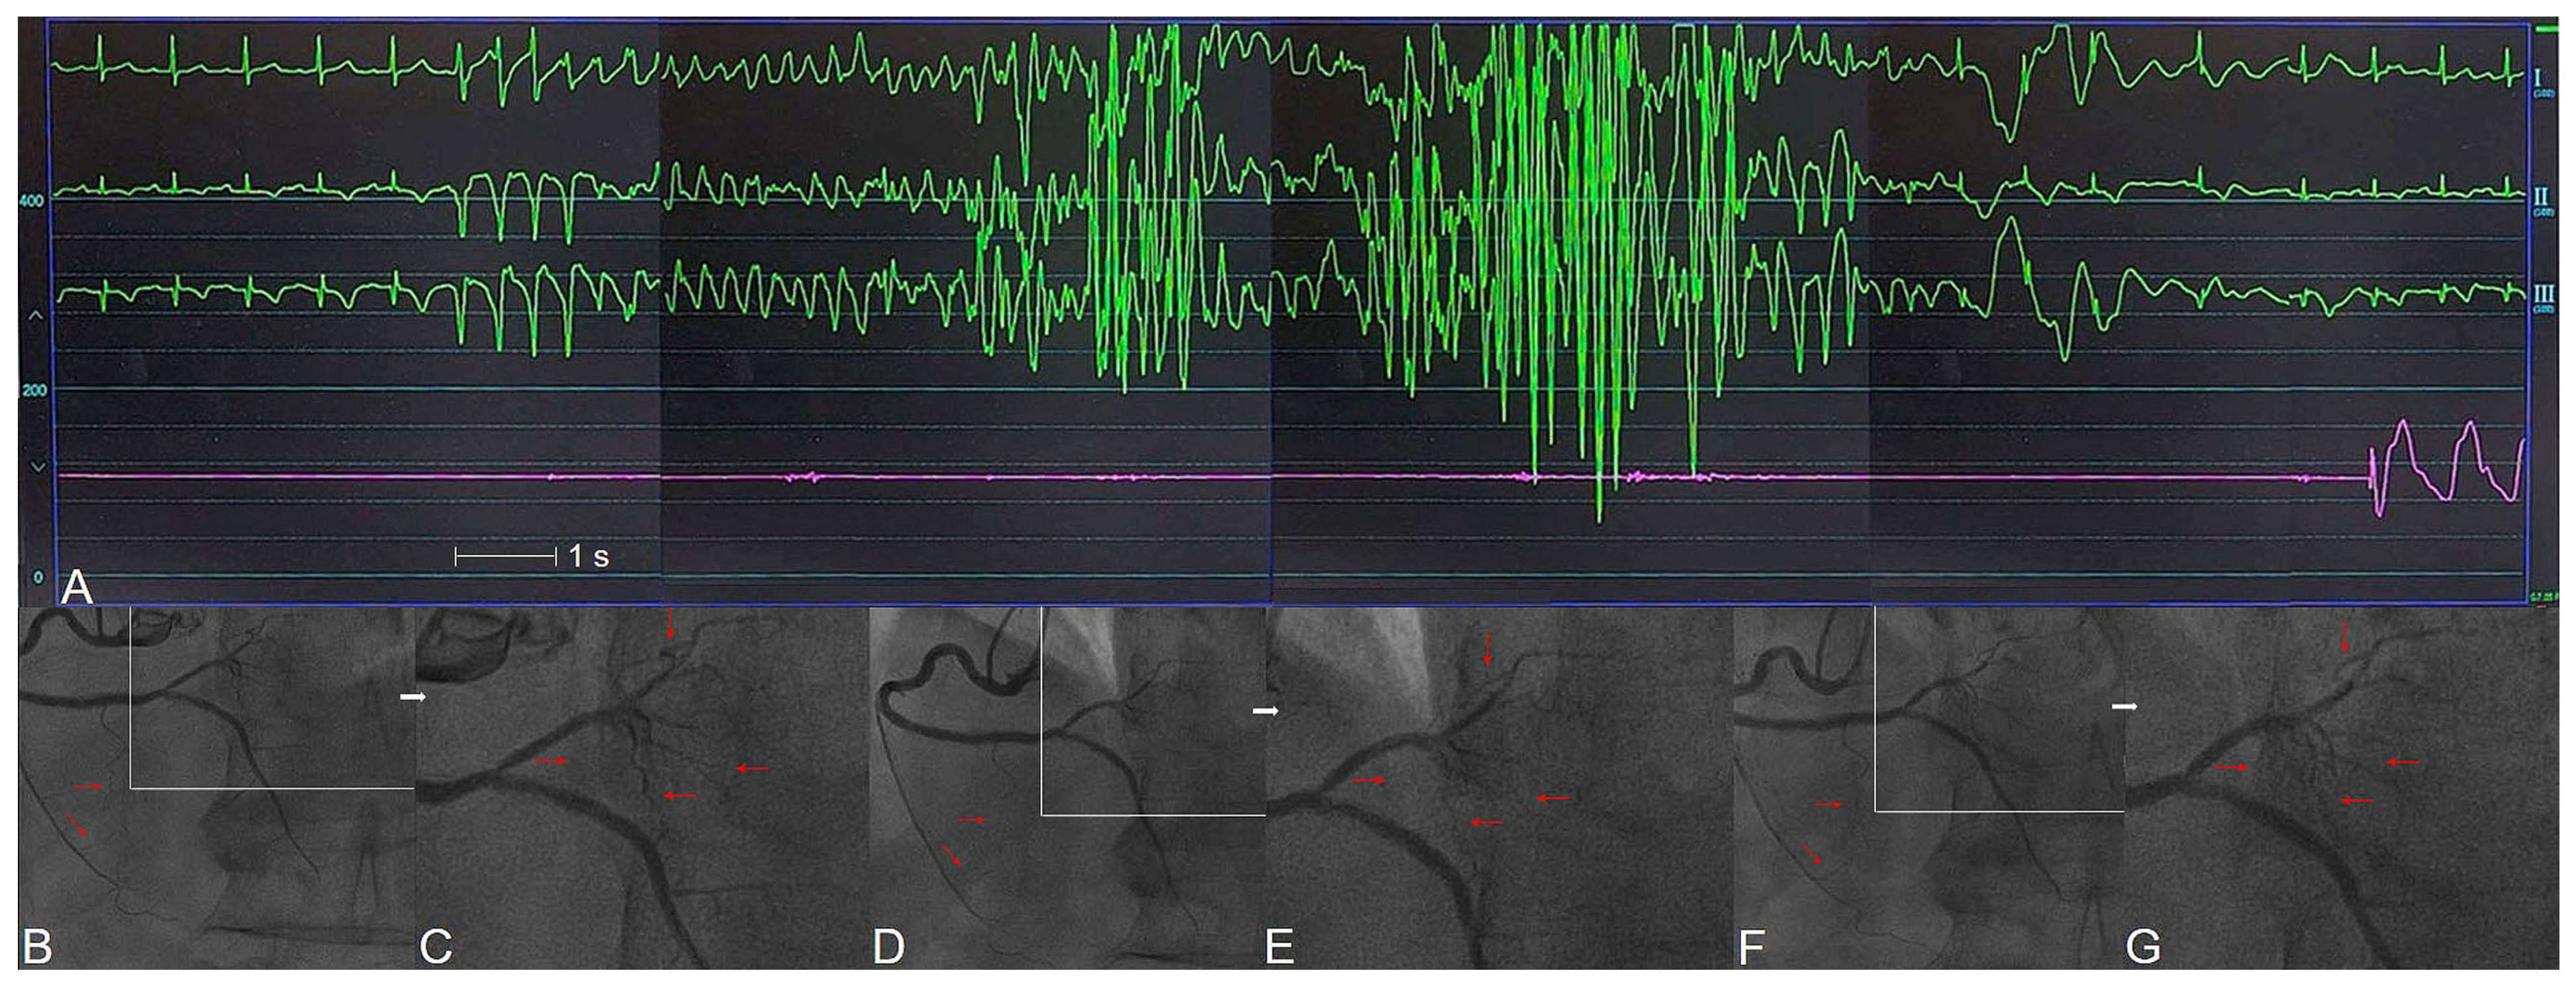

3. Clinical Features of CASHF

4.2. Epicardial CASHF